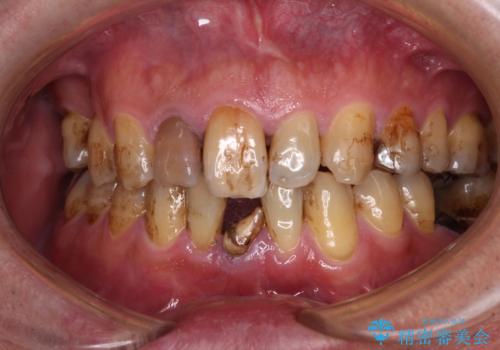

放置した歯列 矯正治療とインプラント治療で劇的に改善

担当医 藤巻太一朗